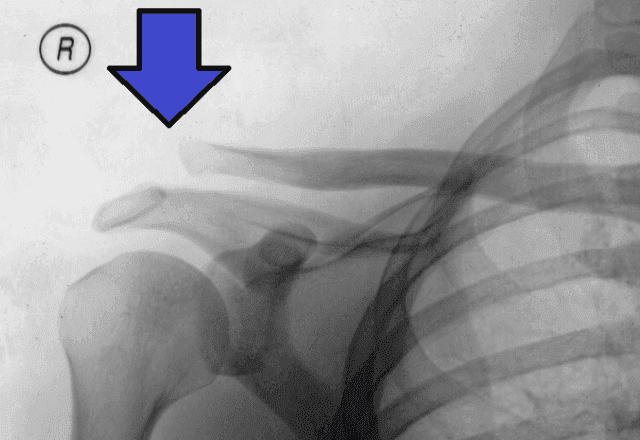

Ponto da lesão na articulação acromioclavicular | Wiki